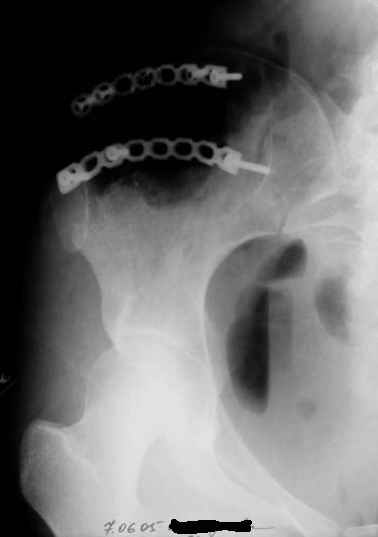

Re: Остеохондрома подвздошной кости

Уважаемые коллеги, больную прооперировали. После выделения остеохондрома резецирована в пределах неизменённой кости. Выявлено, что гребень подвздошой кости не пострадал от опухоли. В результате резекции сформирован сквозной дефект в крыле подвздошной кости треугольной формы 6х7х8 см. В качестве трансплантата использована наружная кортикальная пластинка заднего отдела крыла подвздошной кости.

Трансплантат фиксирован на месте дефекта при помощи шурупов и проволоки. Кровопотеря 550 мл.

На фото этапы операции, R-gr.